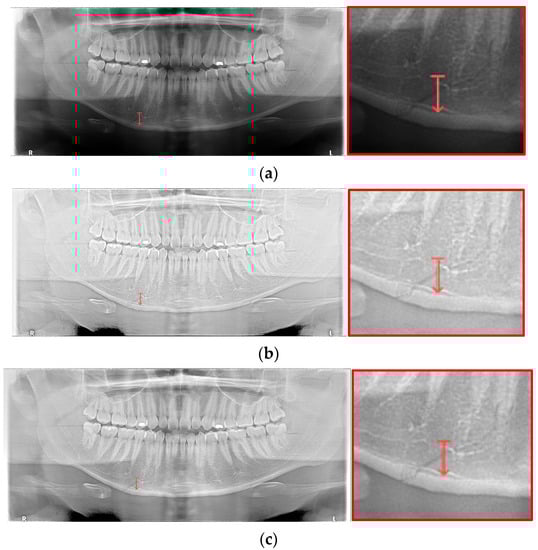

For the case of Figure 12 images, it is possible to check the amount of local contrast improvement from the line profile information. In order to compare the changes in pixel brightness near angle fracture in the normal, SLAT and MLAT panoramic radiographs, the result of line profiles are shown in Figure 14 and Table 7. When comparing the maximum pixel brightness, minimum pixel brightness, average pixel brightness, and standard deviation in the line profile of the straight arrow near the angle fracture site, the normal panoramic radiograph has the largest standard deviation value of 5.6. Due to the characteristics of LAT processing, a dark area increases contrast, but as it becomes a bright area, contrast is maintained or slightly lowered.

Figure 14.

The comparison of SLAT and MLAT processing with line profiler: (a) normal radiograph, (b) SLAT-processed, and (c) MLAT-processed.

However, except for some bright radiograph images, the effect of LAT processing is evident in most dark radiograph images. As shown in Figure 15, most of the LAT-processed radiographs have a high standard deviation value compared to the normal radiographs. In Table 7, the LAT-processed panoramic radiographs shows the higher deviation values of 14.6 and 15.2, which are reasonably more than 9.3 of the normal panoramic radiograph.

Figure 15.

The comparison of SLAT and MLAT processing with line profiler: (a) normal radiograph, (b) SLAT processed, and (c) MLAT processed.